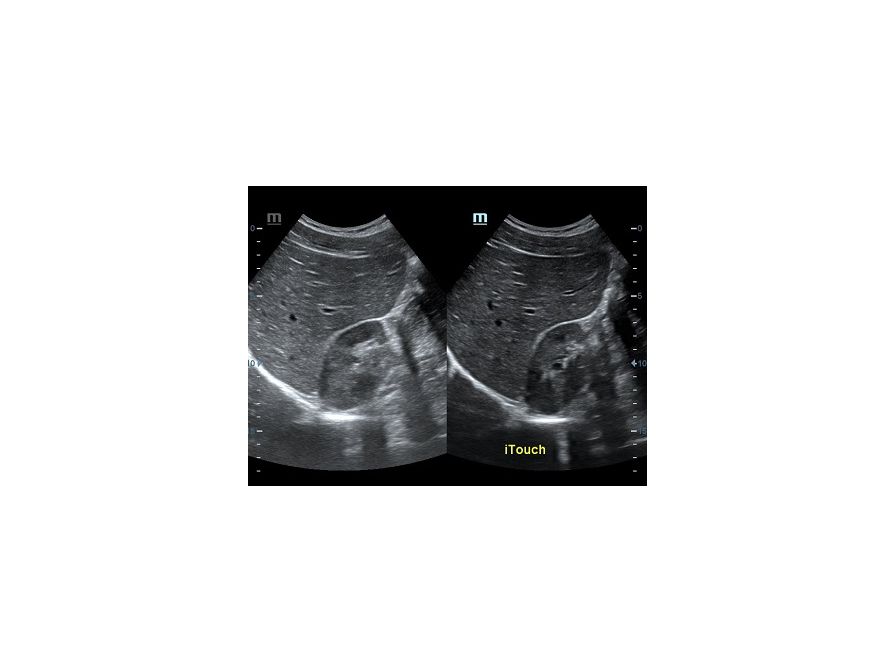

Оптимизация изображения происходит и за счет постобработки. Наиболее часто используемый инструмент - общее усиление (Gain). Усиление делает изображение «ярче», но чем сильнее усиление, тем меньше различия между структурами. Также используются усиление по времени (TGC) и усиление по длине (LGC), которые позволяют изменять отображение на экране послойно, позволяя подсветить гипоэхогенные участки, или, наоборот, снизить визуально эхогенность слишком ярких моментов. Данный вид оптимизации требует много времени, для упрощения работы доктора на приборах Mindray внедрена система автоматической оптимизации - iTouch.